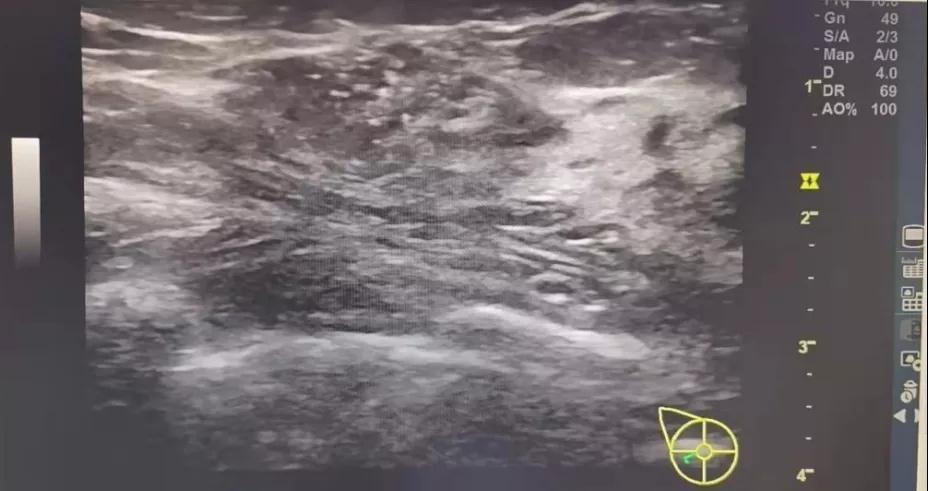

B超:右侧乳腺低回声区,大小约2. 3x1. 3cm(BI-RADS:4b类,提示:乳腺Ca不除外;

术前彩超